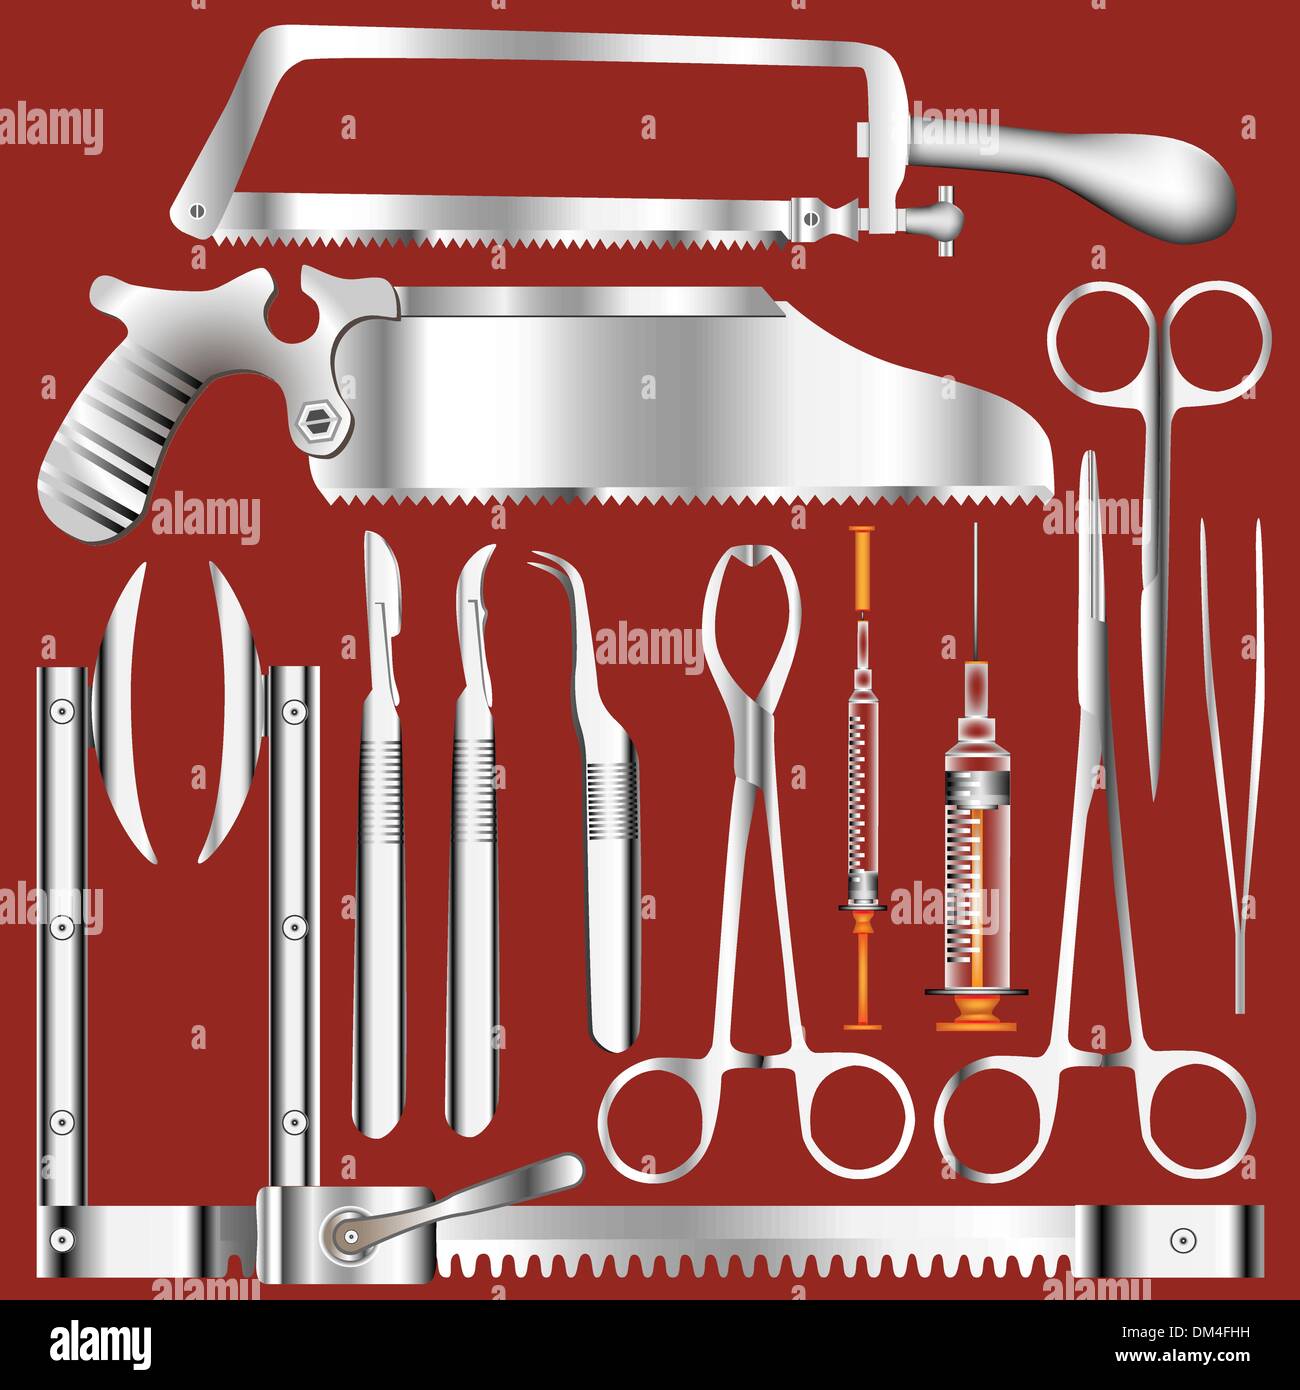

Chirurgische Werkzeug-Set - Edelstahl-Textur Stock Vektorhttps://www.alamy.de/image-license-details/?v=1https://www.alamy.de/chirurgische-werkzeug-set-edelstahl-textur-image64024285.html

Chirurgische Werkzeug-Set - Edelstahl-Textur Stock Vektorhttps://www.alamy.de/image-license-details/?v=1https://www.alamy.de/chirurgische-werkzeug-set-edelstahl-textur-image64024285.htmlRFDM4FHH–Chirurgische Werkzeug-Set - Edelstahl-Textur

Chirurgischer Werkzeugsatz in der Silhouette - Vektorabbildungen Stock Vektorhttps://www.alamy.de/image-license-details/?v=1https://www.alamy.de/chirurgischer-werkzeugsatz-in-der-silhouette-vektorabbildungen-image554936597.html

Chirurgischer Werkzeugsatz in der Silhouette - Vektorabbildungen Stock Vektorhttps://www.alamy.de/image-license-details/?v=1https://www.alamy.de/chirurgischer-werkzeugsatz-in-der-silhouette-vektorabbildungen-image554936597.htmlRF2R6RF85–Chirurgischer Werkzeugsatz in der Silhouette - Vektorabbildungen

Chirurgischer Werkzeugsatz aus Edelstahl - Vektorabbildungen Stock Vektorhttps://www.alamy.de/image-license-details/?v=1https://www.alamy.de/chirurgischer-werkzeugsatz-aus-edelstahl-vektorabbildungen-image554937149.html

Chirurgischer Werkzeugsatz aus Edelstahl - Vektorabbildungen Stock Vektorhttps://www.alamy.de/image-license-details/?v=1https://www.alamy.de/chirurgischer-werkzeugsatz-aus-edelstahl-vektorabbildungen-image554937149.htmlRF2R6RFYW–Chirurgischer Werkzeugsatz aus Edelstahl - Vektorabbildungen